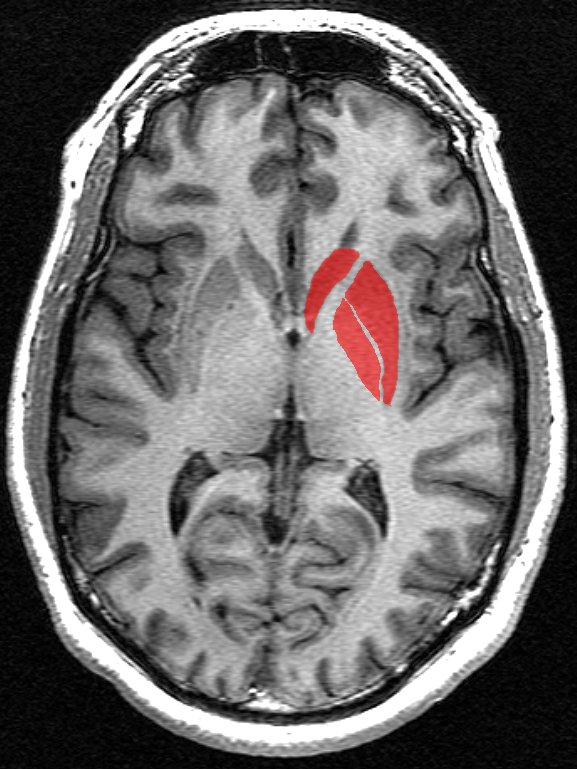

Φωτογραφία: Wikipedia